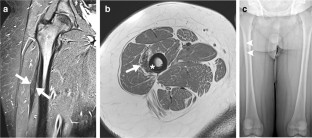

All patients presented with progressive unilateral restricted knee flexion and had multiple imaging studies targeting the knee before diagnosis. Diagnosis in all patients was made on MRI of the thighs, which demonstrated a fusiform low signal intensity structure with muscle-like architecture arising from the anterior or anterolateral proximal femur and blending with the common quadriceps tendon distally. All patients underwent surgical release of the anomalous band with significant functional improvement.

Fig. 1